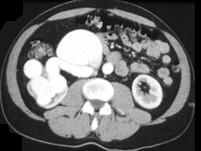

男,18岁,请根据所示图像,选择最可能诊断 ( )A、右侧肾癌B、右肾动静脉畸形C、右肾出血D、右肾囊肿E、右肾积水

问题 男,18岁,请根据所示图像,选择最可能诊断 ( )

选项 A、右侧肾癌 B、右肾动静脉畸形 C、右肾出血 D、右肾囊肿 E、右肾积水

答案 B